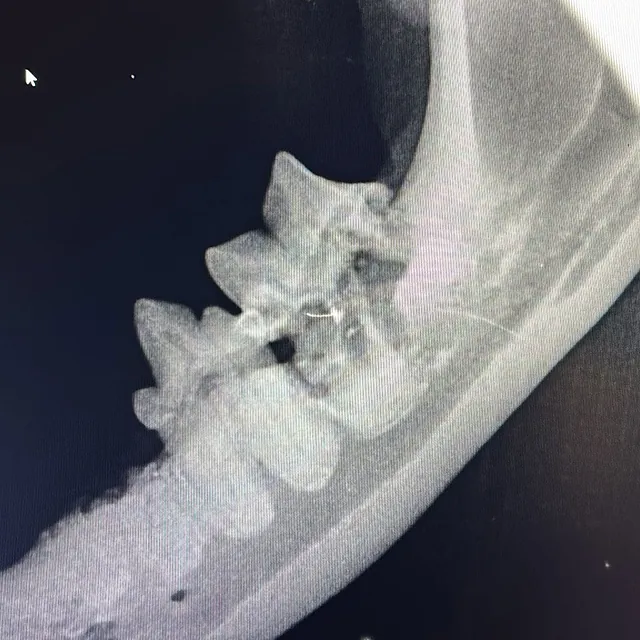

Dentalröntgen – der Goldstandard

• Digitale Zahnradiografie aller Zähne

• Beurteilung von Wurzelresorption, FORL, Abszessen und Frakturen

• Diagnose auch bei äußerlich unauffälligen Zähnen